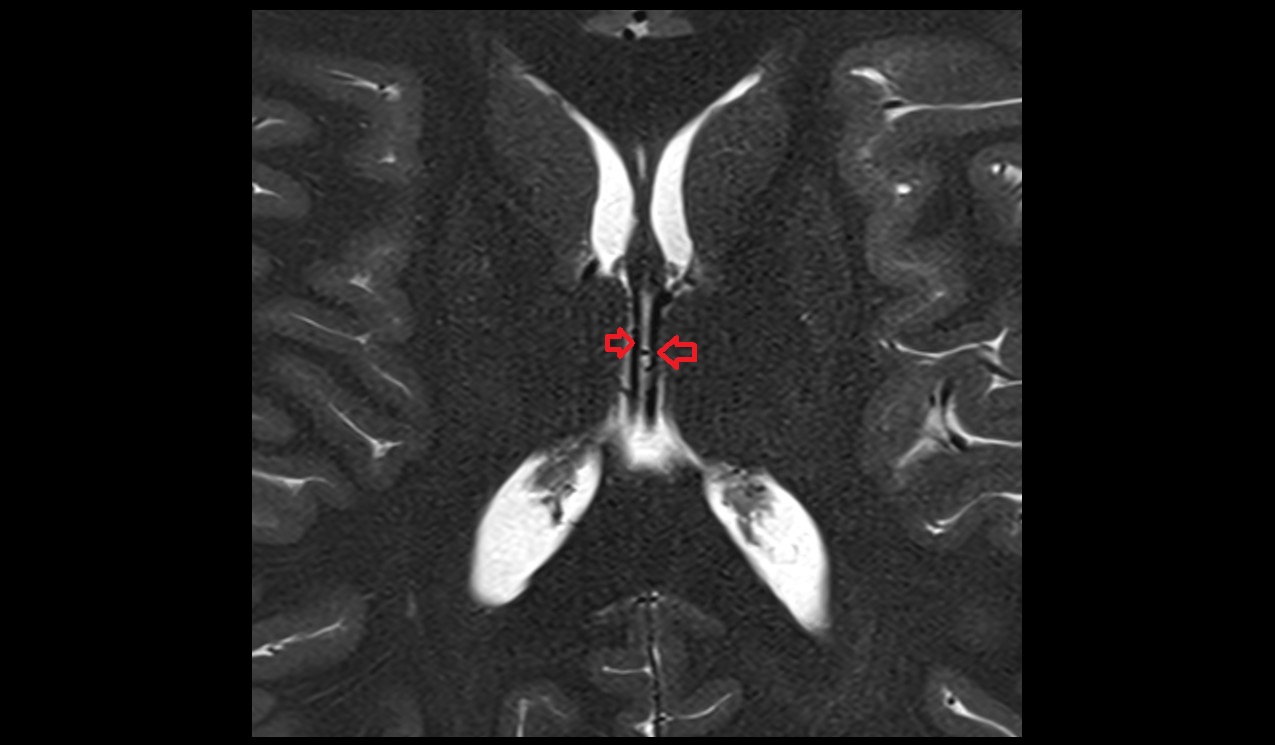

- Interventricular foramen